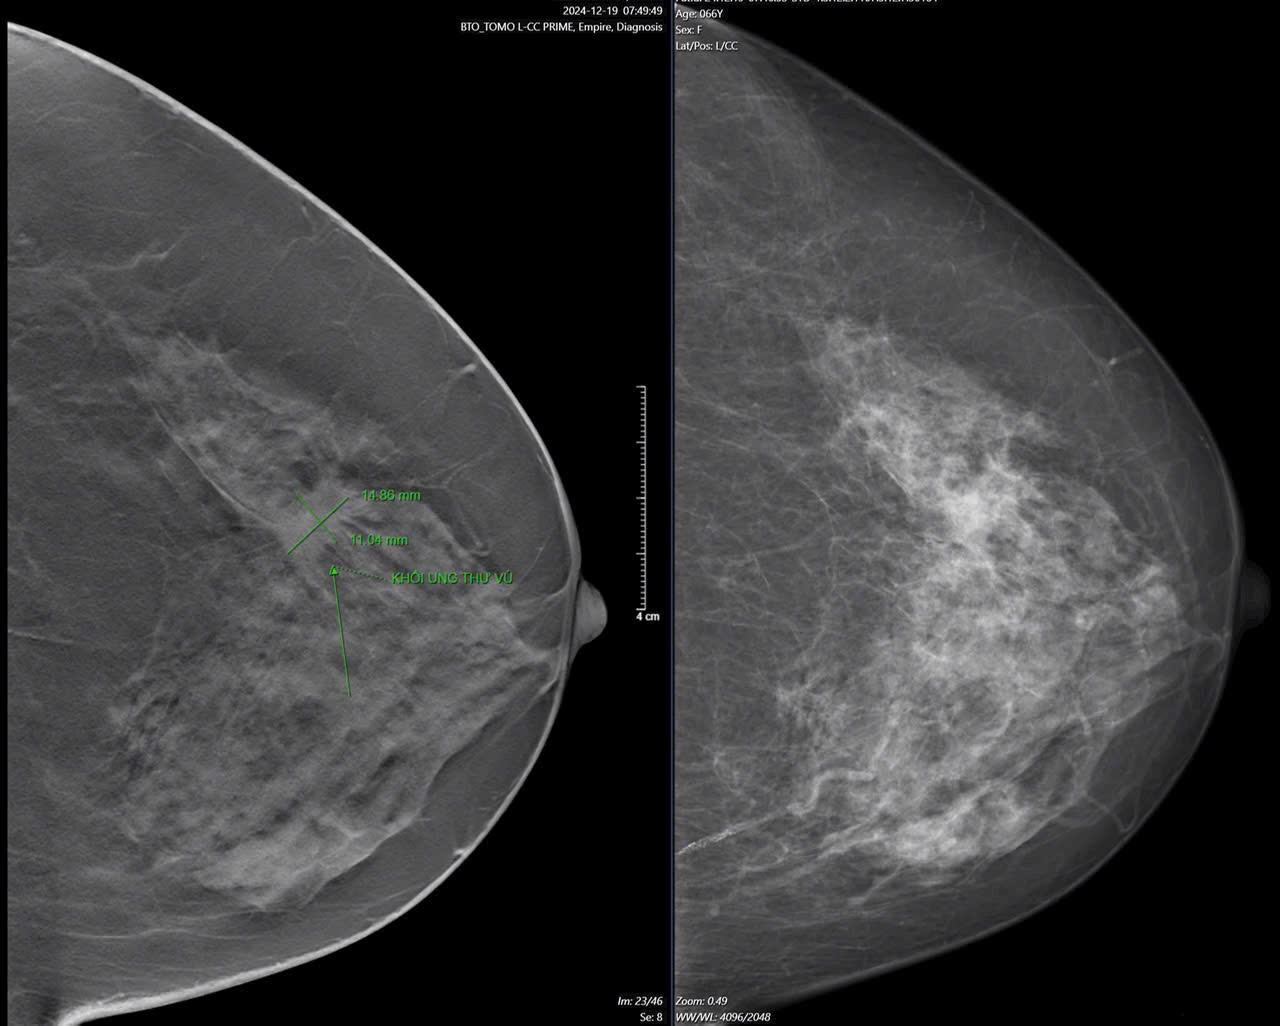

Những Hiểu Lầm Về Phương Pháp Tầm Soát Các Bệnh Lý Tuyến Vú

Tầm soát các bệnh lý tuyến vú đóng vai trò quan trọng trong việc phát hiện sớm các bệnh lý về tuyến vú và ung thư, giúp cải thiện hiệu quả điều...